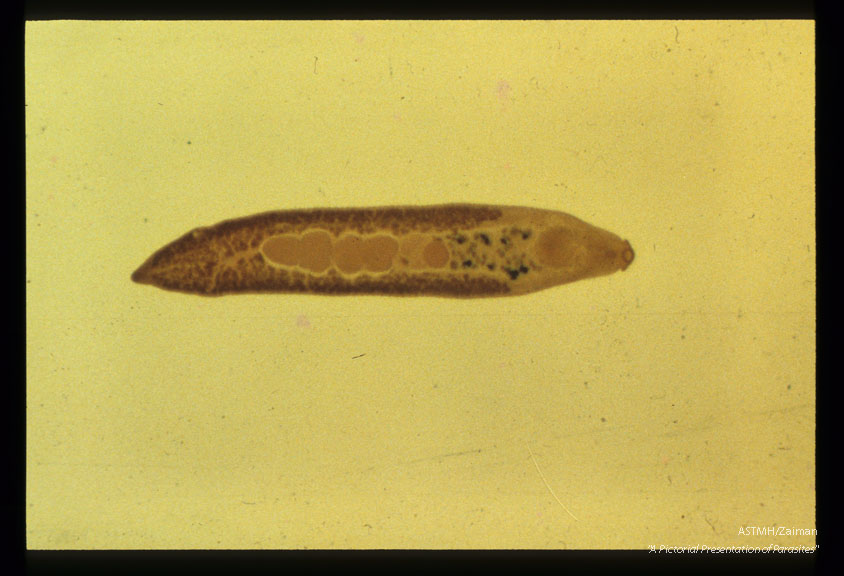

Adult, whole mount.

Echinostoma ilocanum

Description: Adult, whole mount.